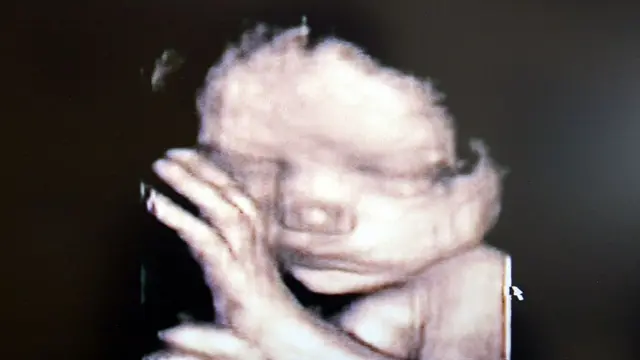

26 வார கருவை கலைக்க உச்ச நீதிமன்றம் அனுமதி

பெண்ணின் கருவில் வளரும் 26 வார சிசு குறைபாடுகளுடன் உள்ளதால், அதை கலைக்க இந்திய உச்ச நீதிமன்றம் அனுமதி அளித்து தீர்ப்பளித்துள்ளது. அரிதான வழக்காக இந்த விவகாரத்தைக் கருதி, இந்த தீர்ப்பை உச்ச நீதிமன்றம் அளித்தது.

அந்த அறிக்கையில், பெண்ணின் கருவில் வளரும் சிசுவுக்கு இதய குறைபாடுகள் உள்ளதாகவும், அந்த சிசு கருவில் தொடர்ந்து வளர்ந்தால், அதன் தாய் மன ரீதியாக காயம் அடைவார் என்றும் குறி்ப்பிடப்பட்டிருந்தது.

மேலும், இதே உடல் வளர்ச்சியுடன் குழந்தை பிறந்தால், அதற்கு பல்வேறு அறுவை சிகிச்சைகள் மேற்கொள்ள நேரிடும் என்றும் அதன் பிறகும் குழந்தைக்கு உடல் பாதிப்புகள் நீடிக்க வாய்ப்புள்ளது என்றும் அறிக்கையில் கூறப்பட்டிருந்தது.